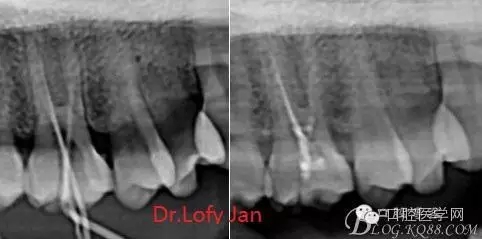

前言:自己做的一些曲面斷層片在未試尖根管治療中的病例整理,發(fā)現(xiàn)問題很多包括自身的,技術(shù)的,還有設(shè)備的問題,予以總結(jié)整理并期待進(jìn)一步提高。

根管治療術(shù)是牙體牙髓疾病治療中最復(fù)雜和最關(guān)鍵的治療項目。根管充填材料抵達(dá)根尖、并能嚴(yán)密堵塞根尖孔,是確保根管治療效果的關(guān)鍵指標(biāo)。為了保證根管充填到位,醫(yī)生需要在術(shù)前照牙片以了解牙根根管的數(shù)量、彎曲程度和長度,在術(shù)中有時需要插針照牙片來精確測量根管長度,術(shù)后必須照牙片以確定是否根管充填到位,如果欠填或超填,就需要重新充填、重新照牙片確認(rèn),直到根管充填到位。所以,在患者接受根管治療時有時會反復(fù)照牙片。

《數(shù)字化根尖片、曲面斷層片、CBCT測量牙齒長度準(zhǔn)確性的比較研究》文中顯示:平行投照數(shù)字化根尖片影像長度和牙齒實際長度之間無顯著性差異(P0.05);數(shù)字化曲面斷層片影像長度和牙齒實際長度之間有顯著性差異(P0.05),平均失真率為17.05%。CBCT冠狀面測量結(jié)果中除上頜前磨牙區(qū)、下頜前磨牙區(qū)與真實長度差異無統(tǒng)計學(xué)意義(P0.05)外,其余6個分區(qū)差異均有統(tǒng)計學(xué)意義(P0.05);矢狀面測量結(jié)果中上頜磨牙區(qū)、下頜磨牙區(qū)、下頜前磨牙區(qū)、下頜尖牙區(qū)、下頜前牙區(qū)與真實長度比較差異均有統(tǒng)計學(xué)意義(P0.05)。結(jié)論平行投照數(shù)字化根尖片較曲面斷層片和CBCT能更加精確地反映牙齒的真實長度。

病例分析:曲面斷層片在x線輔助診斷與檢查中目前大多數(shù)文獻(xiàn)和著作都建議只能作為初診拍片檢查手段,不能作為終末疾病的確診與手術(shù)療效的評價指標(biāo),臨床大部分中小型門診都因為設(shè)備不齊全導(dǎo)致信息偏差很大。